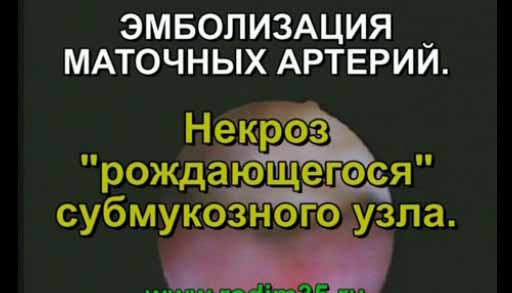

Вашему вниманию предлагаются видеозаписи лекций выдающихся врачей и преподавателей, выступления на конференциях, съемки хирургических операций, полезные советы по сохранению здоровья, красоты и профилактике заболеваний, переводы зарубежных медицинских видеоматериалов, медицинские статьи и блоги врачей. Вам также могут быть интересы отзывы о лекарствах.